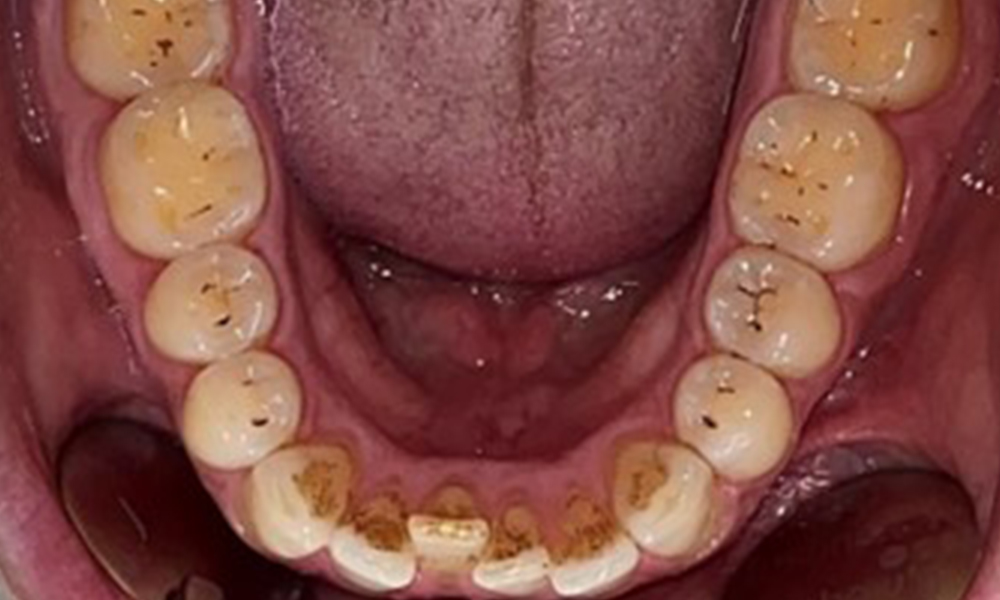

Il n'y a pas eu de résultats pathologiques extra-oraux. Lors de l'examen intrabuccal, l'inspection de la vue frontale a révélé une décoloration brunâtre près de la gencive kératinisée et à la transition vers la muqueuse mobile (Fig. 2), qui pourrait être attribuée à la consommation de nicotine. Des lésions blanchâtres de la muqueuse ont été observées sur le palais, en particulier près des surfaces palatines des molaires maxillaires, ce qui indique une kératinisation accrue et peut également être attribué à la consommation de nicotine. La langue était recouverte d'un enduit amovible blanc et brunâtre.

Le patient a une dentition complète avec un total de 28 dents. Il y avait des érosions et des attritions notables. (Fig. 4, Fig. 5). En raison du bruxisme, le patient a porté pendant de nombreuses années une attelle avec une gouttière ajustée la nuit. Les érosions ont été causées par une consommation prolongée de boissons isotoniques. Aucune perte d'os parodontal ou carie active n'a été observée.